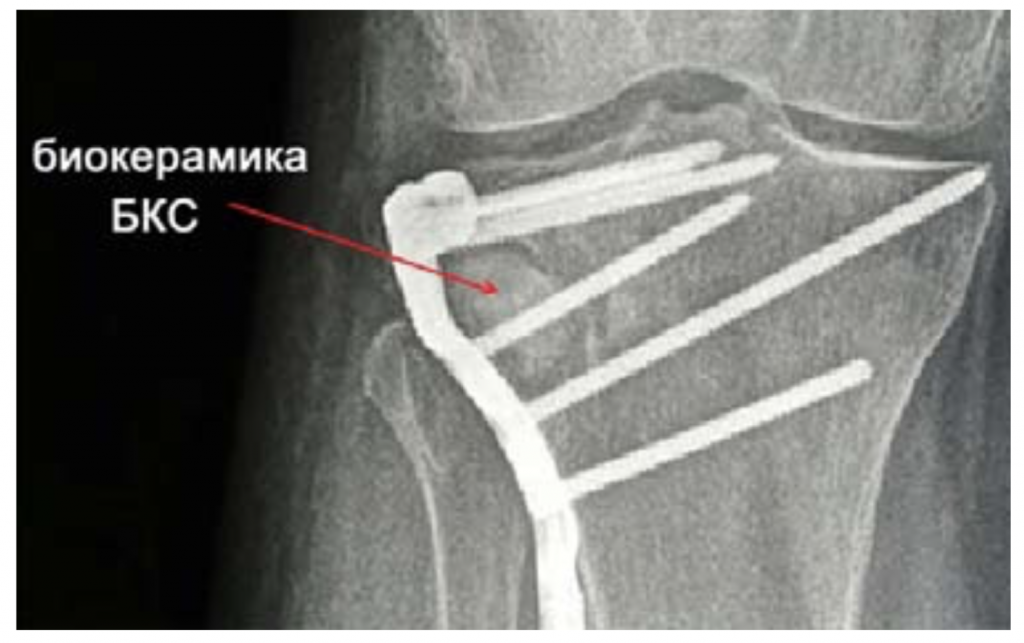

Специалисты ЦНИИАГ разработали два вида биокерамических изделий − «БКС» и «НИС-НХ-Р». Биокерамика «БКС» в виде блоков, пластин, гранул и порошков различной дисперсности применяется для замещения дефектов костных тканей в травматологии, челюстно-лицевой хирургии и хирургической стоматологии. В течение года после операции проходит процесс отсеогенеза, и биокерамические имплантаты срастаются с костной тканью организма, что можно наблюдать с помощью рентгенографии.